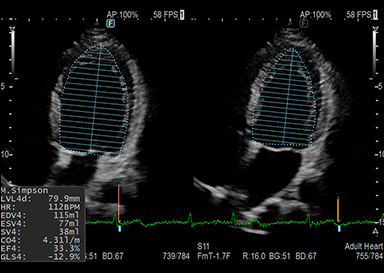

頸部(動静脈・甲状腺)、心臓、腹部(肝臓・胆のう・膵臓・脾臓・腎臓・膀胱・腹部大動脈等)、下肢(動脈・静脈)等が観察できる検査です。

超音波機器について

超音波検査では機械の性能が画質を決定します。性能の良い超音波機器での検査ではより詳細な情報が得られます。